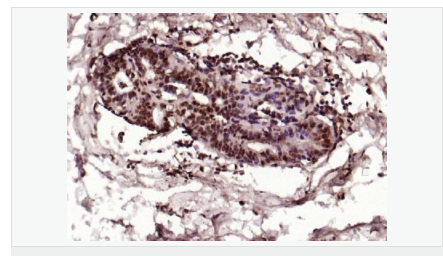

交叉反應(yīng):Human,Mouse,Rat(predicted:Dog,Pig,Rabbit,GuineaPig) 推薦應(yīng)用:IHC-P,IHC-F,ICC,IF,Flow-Cyt,ELISA

| 產(chǎn)品應(yīng)用 | ELISA=1:5000-10000 IHC-P=1:100-500 IHC-F=1:100-500 Flow-Cyt=1μg/Test ICC=1:100 IF=1:100-500 (石蠟切片需做抗原修復(fù)) not yet tested in other applications. optimal dilutions/concentrations should be determined by the end user. |